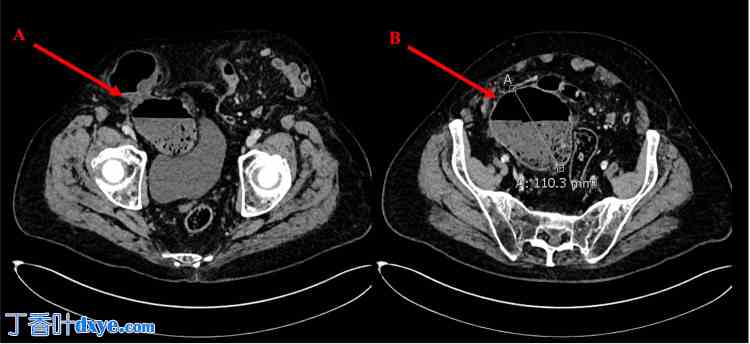

图2. 盆腔增强CT轴位图像。图中显示双侧腹股沟疝较大。

标签 A 显示远端降结肠和盲肠通过挤压性直接缺损疝入疝囊。标签 B 显示盲肠扩张至 11 cm,伴有粪便排出和少量周围游离液体。